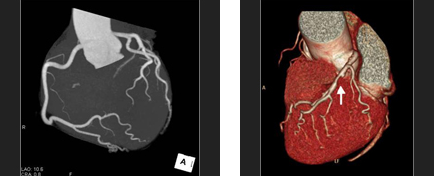

CTコロノグラフィー検査

CTコロノグラフィー検査とは、CTを用いた大腸検査の総称です。拡張や鎮痙剤で腸管の蠕動運動の抑制を行い、注腸X線造影検査や大腸内視鏡と同様の前処置をしたうえで撮影し専用の大腸解析ソフトを用いて、様々な再構成画像を作成し評価します。